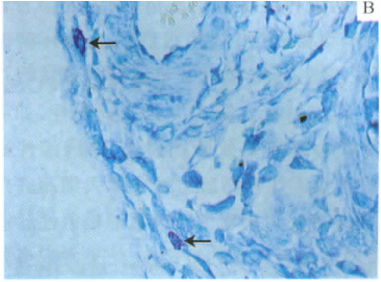

部分实验图展示

肥大细胞特殊染色,箭头所指为脱颗粒状态的肥大细胞